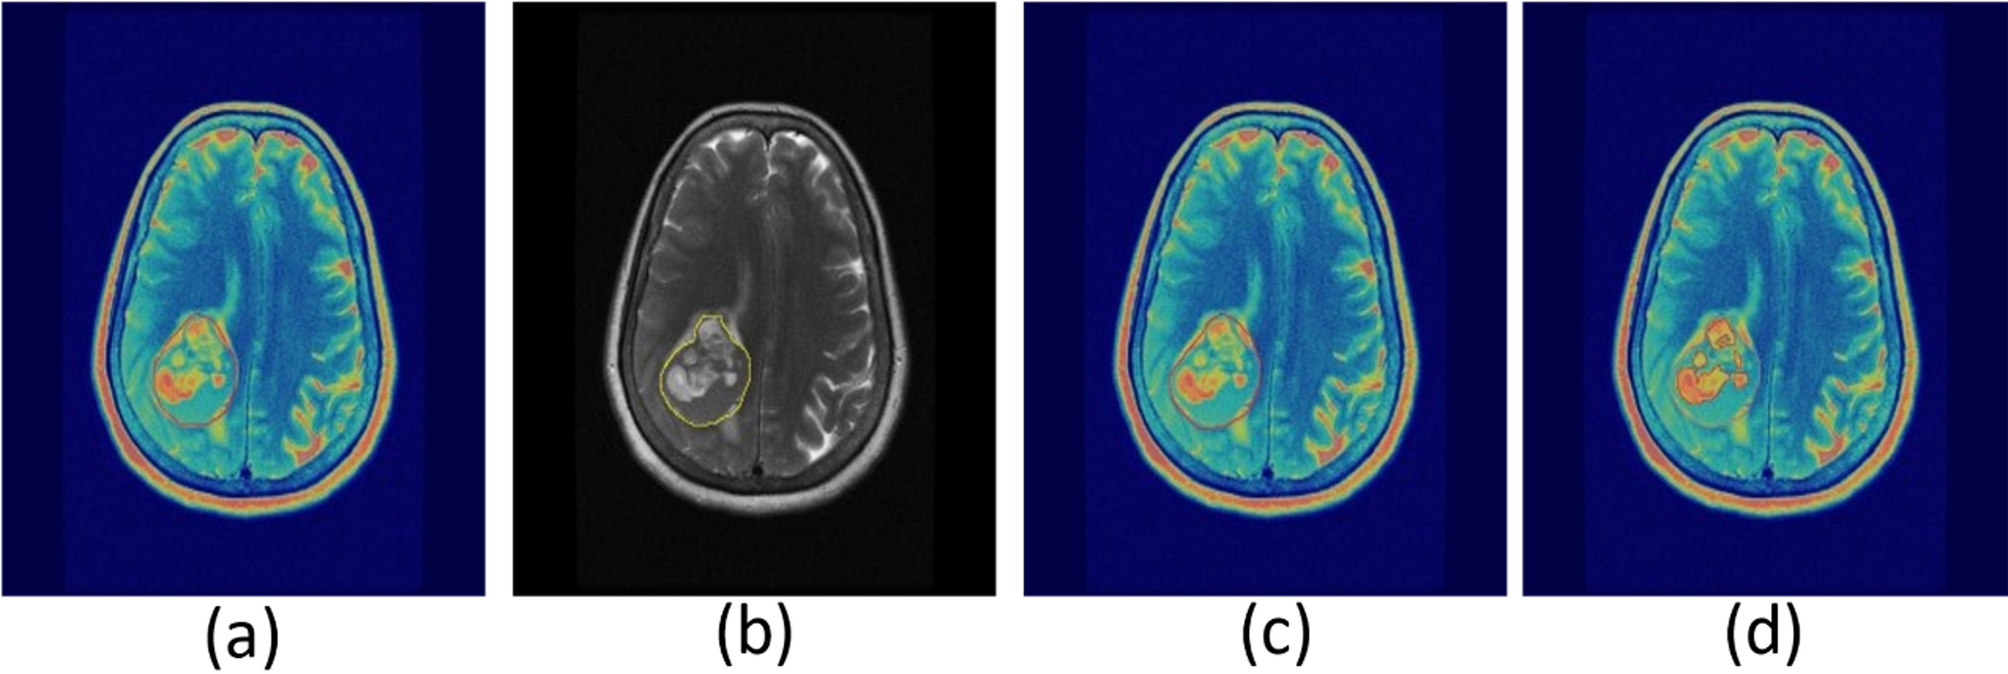

Fig. 2

Refining PET/MRI imaging tumor delineation by excluding skull bone and meninges. PET delineation (a) copied onto MRI image (b) for defining boundaries. MRI used to exclude skull bone and meninges from ROI (c), followed by refinement with adaptive thresholding (d).